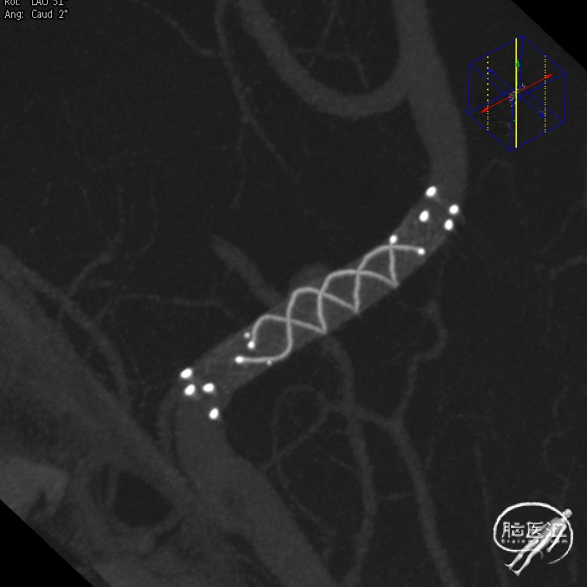

经右侧桡动脉通路,赛诺神畅 6F-105 APEX TRA®经桡远端通路导引导管内衬SIM2导管、泥鳅导丝,左侧颈内动脉顺利直接到位海绵窦段行3D造影。

动脉瘤无明显变化;A1开口角度较大,输送支架需注意导管是否失位。

微导丝、支架微导管配合超选。

支架尾端避开开窗。

释放过程,通路导管稳定。

支架头端锚定后造影定位。

50%-50%规律,支架尾端着落点可覆盖动脉瘤同时避开转角。

支架释放过程,通路导管稳定支撑。

术后影像。